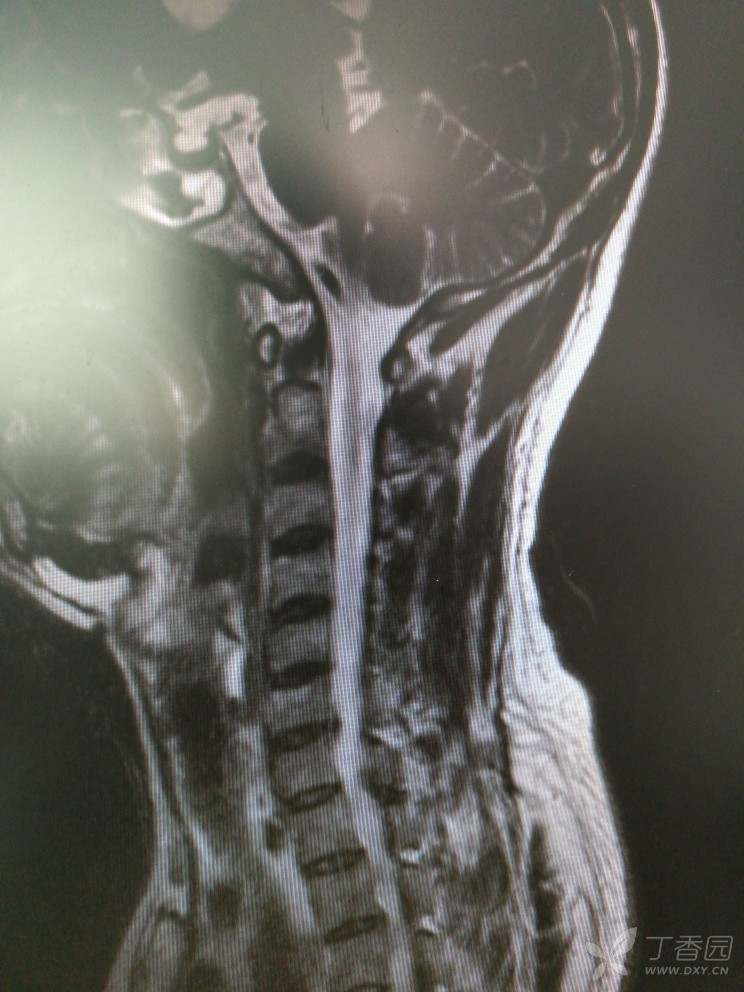

入院查MRI

我想问还是考虑L4/5 L5/S1椎间盘的变性引起的吗?